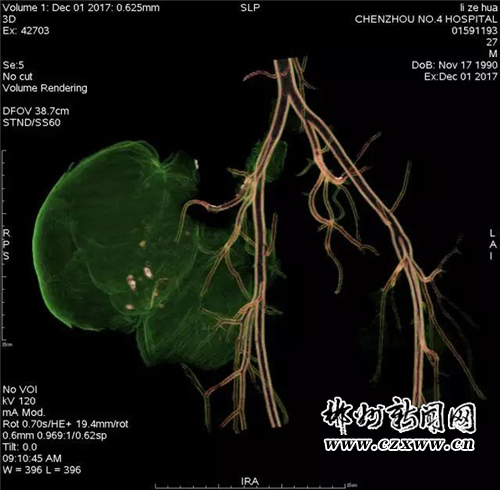

近日,患者感觉肿块突然增大并伴疼痛,觉得不能再耽搁了,遂抱以试试看的心态来我院就诊。入住普外科后,科主任李洪春主任医师亲自接诊并仔细为患者检查,患者右侧臀部外侧见约12*14*10cm大小肿物,不规则型,质软,压痛,活动欠佳,边界清,皮肤无溃烂。穿刺可抽出血性液体。立即予以完善臀部CT。

为进一步明确诊断与治疗,科室立即申请医院副院长放射科主任郑海军主任医师会诊探讨,经讨论认为:患者血管瘤营养支可能来自右侧髂内动脉分支臀上、下动脉,血运丰富,血流量大,一旦再次出血,后果将不堪想象,应尽快安排手术取出该“定时炸弹”。可问题是,该肿块血运如此丰富,术中出血不可估量,该如何避免呢?此时,李洪春主任立即联系介入科主任薛小刚副主任医师会诊,会诊后立即行血管介入栓塞术,以先切断肿块的血运,防止术中大出血。行血管介入栓塞术后,再在做好其他术前准备和积极备血的前提下,普外科予患者行右侧臀部巨大假性动脉瘤切除术。